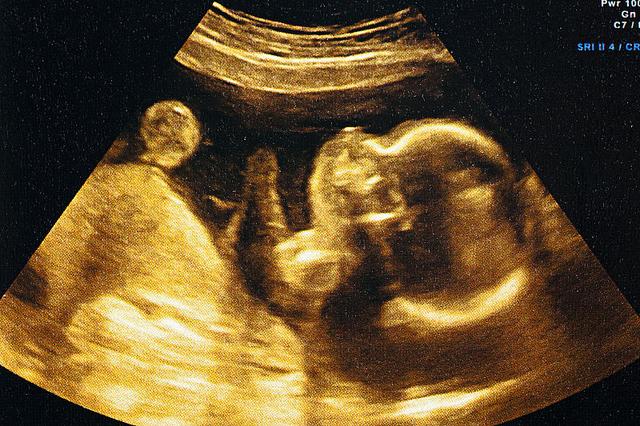

13三体综合征 胎儿

13三体综合征

听过21三体综合征,那么你知道"13三体综合征"吗?